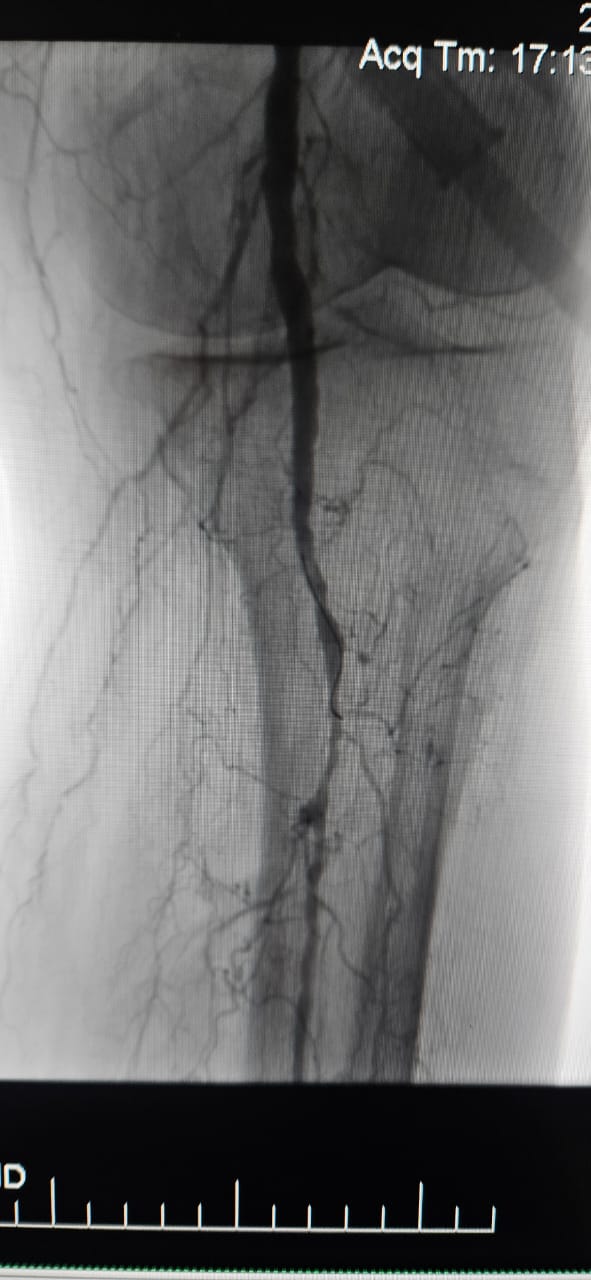

Klinischer Fall im Rampenlicht: Chronische CLI-Okklusion mit ThorCrack-IVL behandelt

Wir freuen uns, einen erfolgreichen Fall aus einem Krankenhaus in Batumi, Georgia, zu teilen, in dem eine 78-jährige Patientin mit kritischer Extremitäten ischämie (CLI), die durch einen chronischen vollständigen Verschluss der Arterie der unteren Extremitäten verursacht wurde, nach der Behandlung mit dem ThorCrack Peripheral IVL Balloon Dilatation Catheter System.

Dieser Fall unter streicht den klinischen Wert der intra vaskulären Litho tripsie (IVL) bei der Behandlung komplexer CLI-Fälle mit chronischer Okklusion mit langem Segment-insbesondere bei Patienten mit starker Verkalkung, bei denen herkömmliche Ballons oder Atherektomie geräte möglicher weise eine begrenzte Wirksamkeit aufweisen.

Wir sind stolz darauf, dass ThorCrack IVL Ärzte auf der ganzen Welt befähigt, verkaldete Läsionen zu überwinden, die Perfusion wieder herzustellen und die Patienten ergebnisse bei komplexen peripheren arteriellen Erkrankungen zu verbessern.